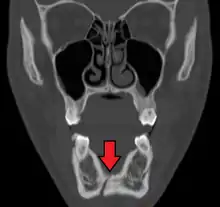

Computed tomography is the most sensitive and specific of the imaging techniques. The facial bones can be visualized as slices through the skeletal in either the axial, coronal or sagittal planes. Images can be reconstructed into a 3-dimensional view, to give a better sense of the displacement of various fragments. 3D reconstruction, however, can mask smaller fractures owing to volume averaging, scatter artifact and surrounding structures simply blocking the view of underlying areas.

3D CT reconstruction of mandible fracture, white arrow marks fracture, red arrow marks moderate displacement and open bite